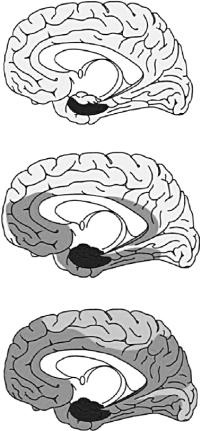

К тому же исследования, проведенные франкфуртским анатомом Хайко Брааком, давно доказали, что болезнь Альцгеймера (см. следующую главу) начинается в области гиппокампа и распространяется далее вдоль многочисленных соединений с другими участками коры головного мозга (см. рис. 1.10).

1.10. Распространение болезни Альцгеймера. На ранних стадиях (вверху) затронута только область гиппокампа, в средних стадиях (в середине) — те участки коры головного мозга, которые связаны с гиппокампом, а в поздней стадии (внизу) — практически весь головной мозг.